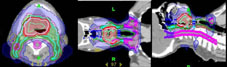

目前針對頭頸部治療中,強度調控放射線治療(IMRT)是多數醫院所採用的治療技術,主要在於IMRT可提供較傳統更精準的腫瘤治療與降低重要器官的傷害。本院目前擁有導航螺旋刀與強度調控放射線治療,我們兩年多來的治療經驗發現,導航螺旋刀比強度調控放射線治療技術能提供更好的腫瘤順形度治療 (圖1)。由於口咽癌特殊的位置與導航螺旋刀的特性,導航螺旋刀更適合運用在此類頭頸癌的患者身上(圖2)。

圖2 運用導航螺旋刀設計與治療口咽癌的患者。